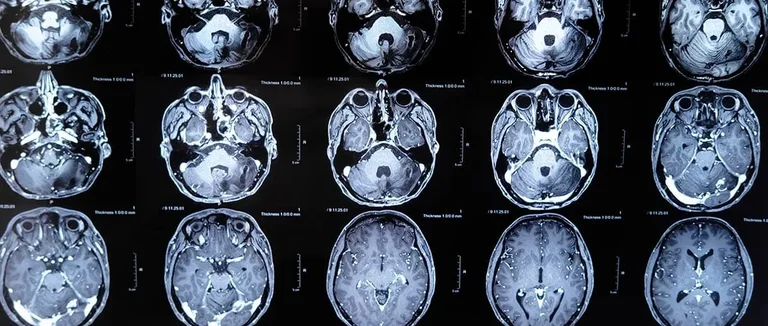

Les scanners CT combinent rayons X et informatique pour créer des images détaillées. Ils sont cruciaux pour diagnostiquer de nombreuses conditions, y compris les tumeurs cérébrales.

Fonctionnement d'un Scanner CT

Un scanner CT tourne un faisceau de rayons X autour du corps. Il capture des images à différents angles. Un ordinateur traite ces images pour créer des coupes transversales précises.

Les rayons X pénètrent les tissus du cerveau selon leur densité. Les os, qui sont denses, absorbent plus de rayons X et apparaissent blancs sur les images. Les tissus moins denses, comme la matière grise, absorbent moins et apparaissent en gris.

La visibilité des tumeurs sur les images CT dépend de plusieurs éléments. La taille et la densité de la tumeur jouent un grand rôle. Les tumeurs plus grandes et avec des calcifications sont plus visibles.

Les images CT montrent clairement les structures du cerveau. Elles aident les médecins à repérer les anomalies. Mais, certaines tumeurs petites ou de faible densité peuvent être plus difficiles à voir.

Des recherches montrent que les scanners CT détectent les tumeurs cérébrales avec une sensibilité de 73 à 97%. Cette sensibilité varie selon la taille et le type de tumeur. Elle dépend aussi de la qualité de l'équipement.

Une étude a montré que la précision des scanners CT dépend de plusieurs facteurs. La résolution de l'image et l'expertise du radiologue sont cruciales. Cela montre l'importance d'une bonne interprétation des images.